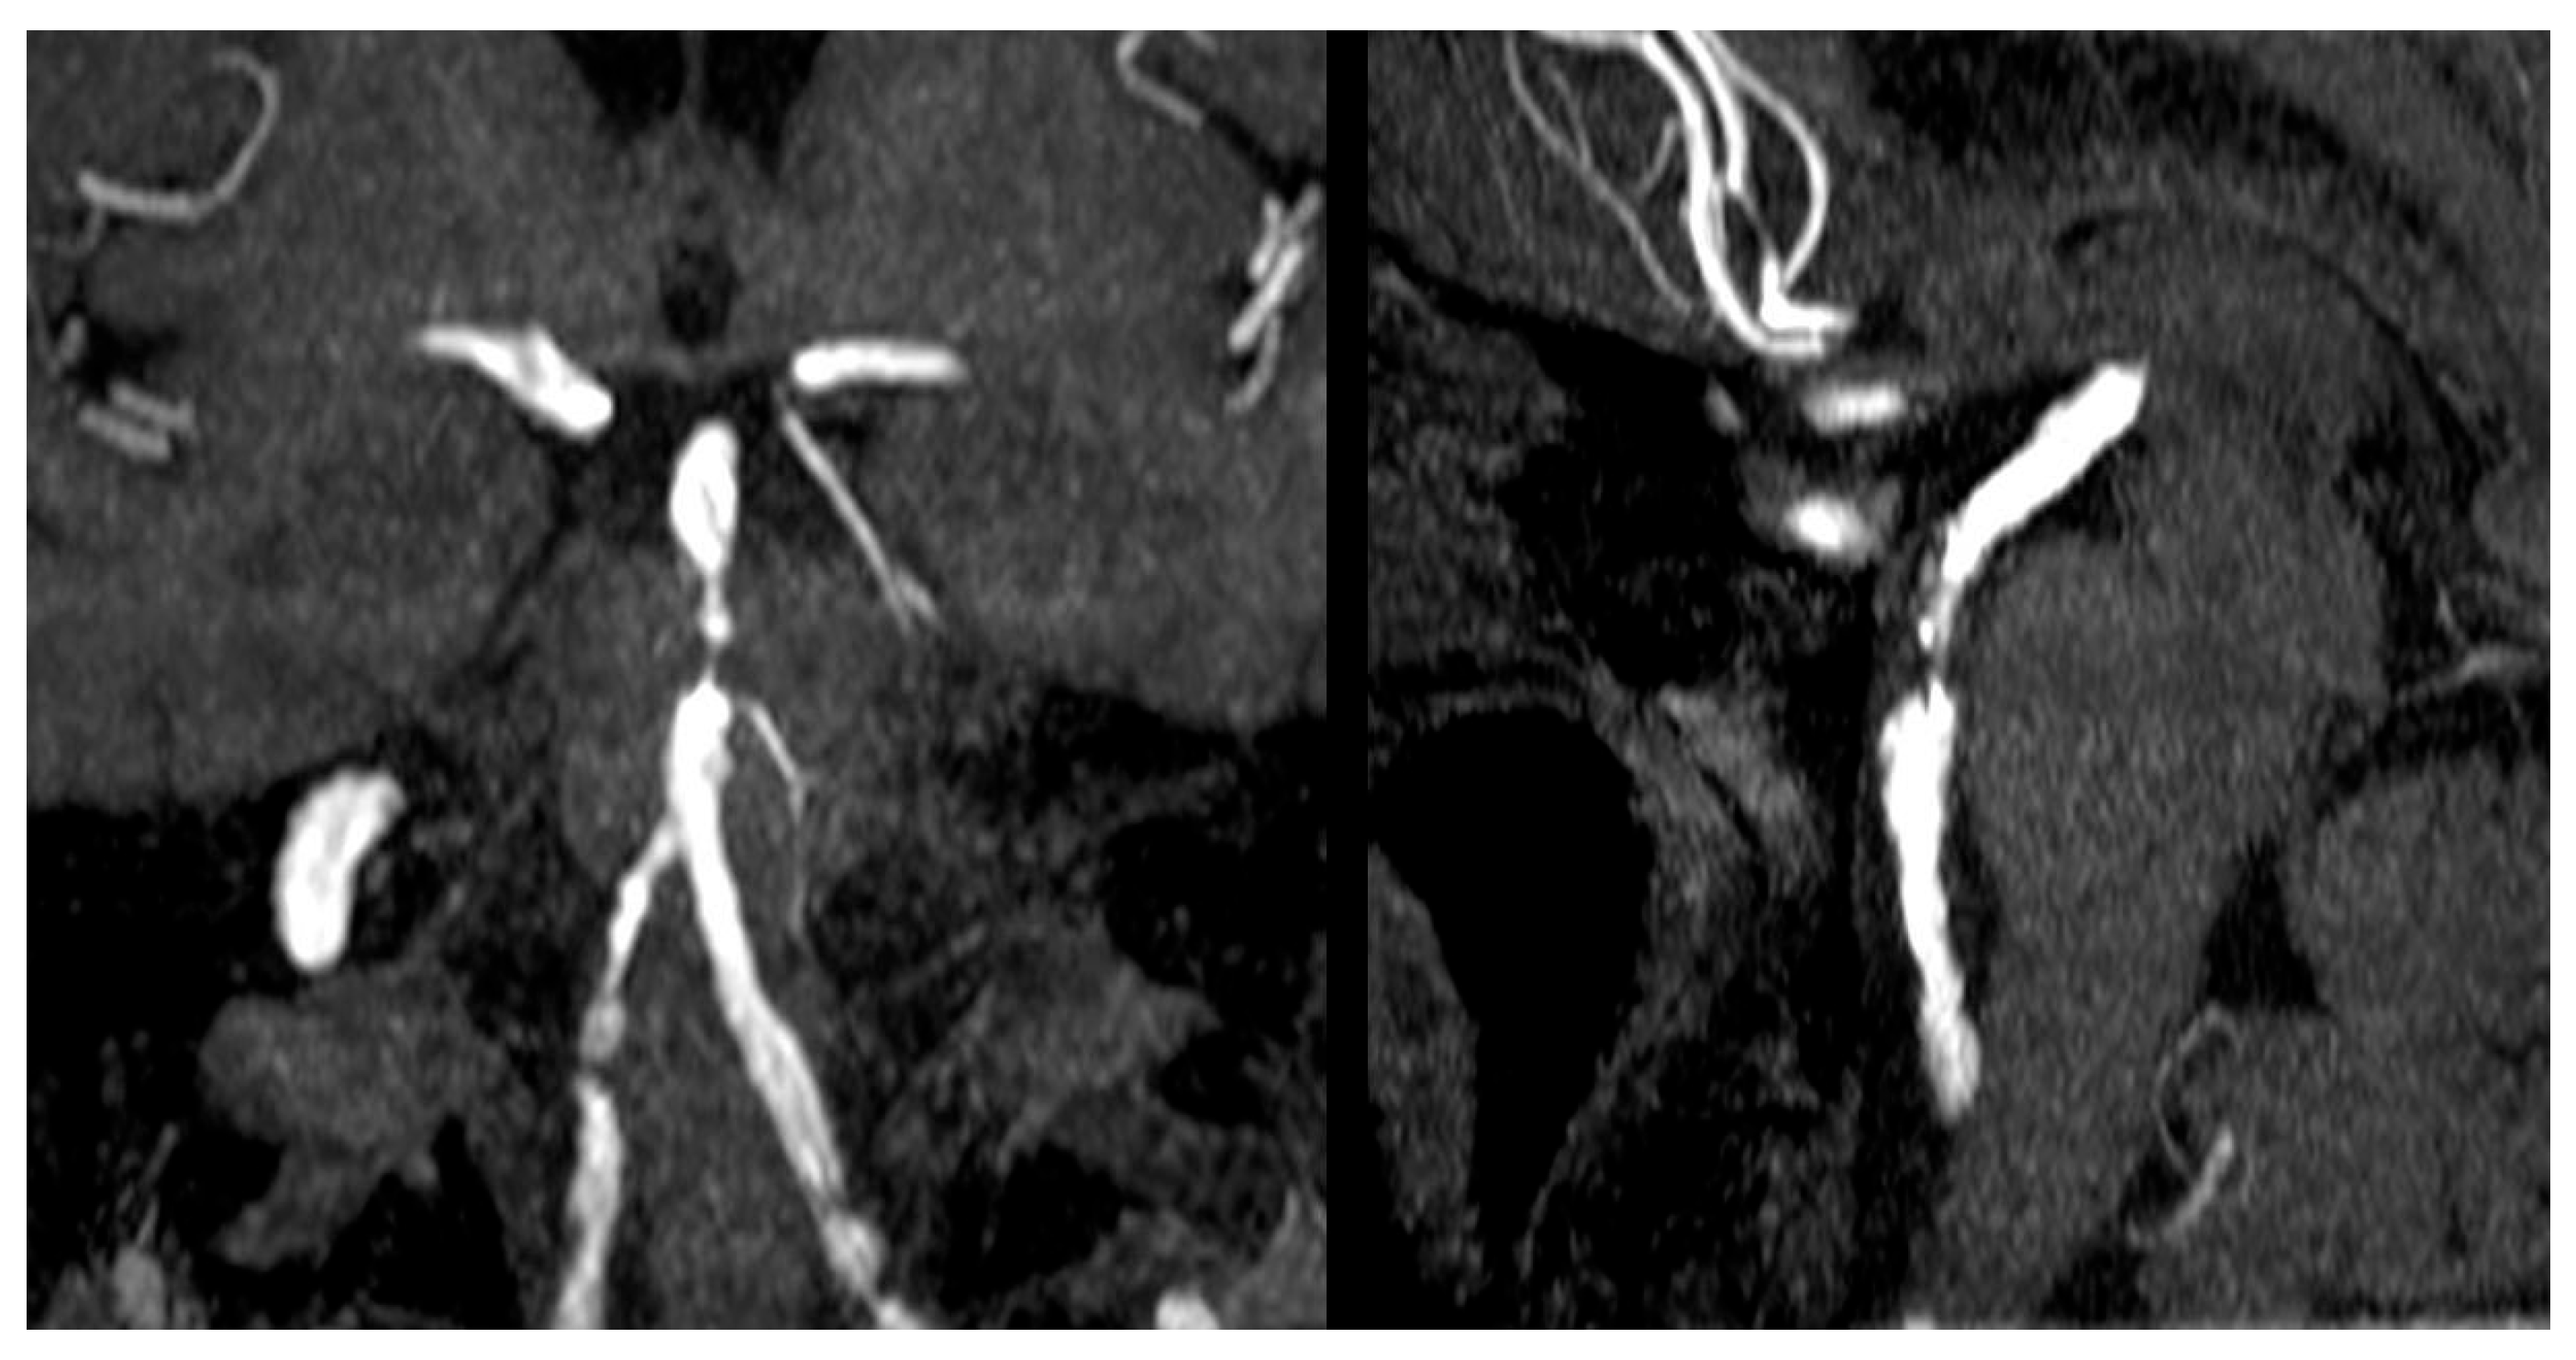

- Di Muzio, B. Basilar Artery Stenosis. Case Study, Radiopaedia.org. Available online: https://doi.org/10.53347/rID-30288 (accessed on 11 June 2025).